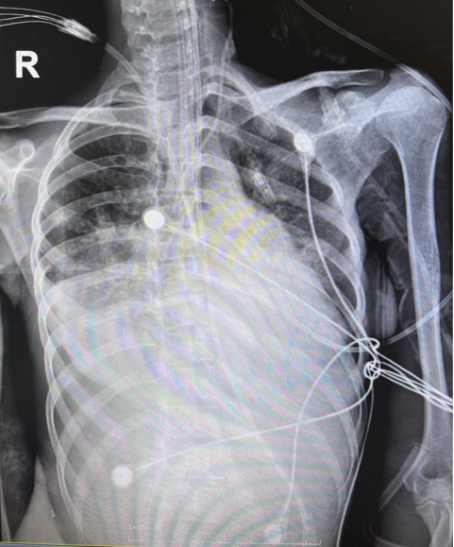

7月9日全身多发紫癜,弥散性血管内凝血(DIC)趋势。床旁胸片见右肺多发类结节样改变(图2)。血常规及生化等检查示:WBC 17.2×109/L,NEU% 92.8%,Hb 56 g/L,PLT 23×109/L,CRP 228.93 mg/L;ALB 21.6 g/L,BUN 41.7 mmol/L,Cr 185.5 μmol/L;CTnT 0.163 pg/ml;PT 16.7 s,APTT 45.5 s,D-二聚体8.28 μg/ml。

图2 患者胸部X线片(2022年7月9日)